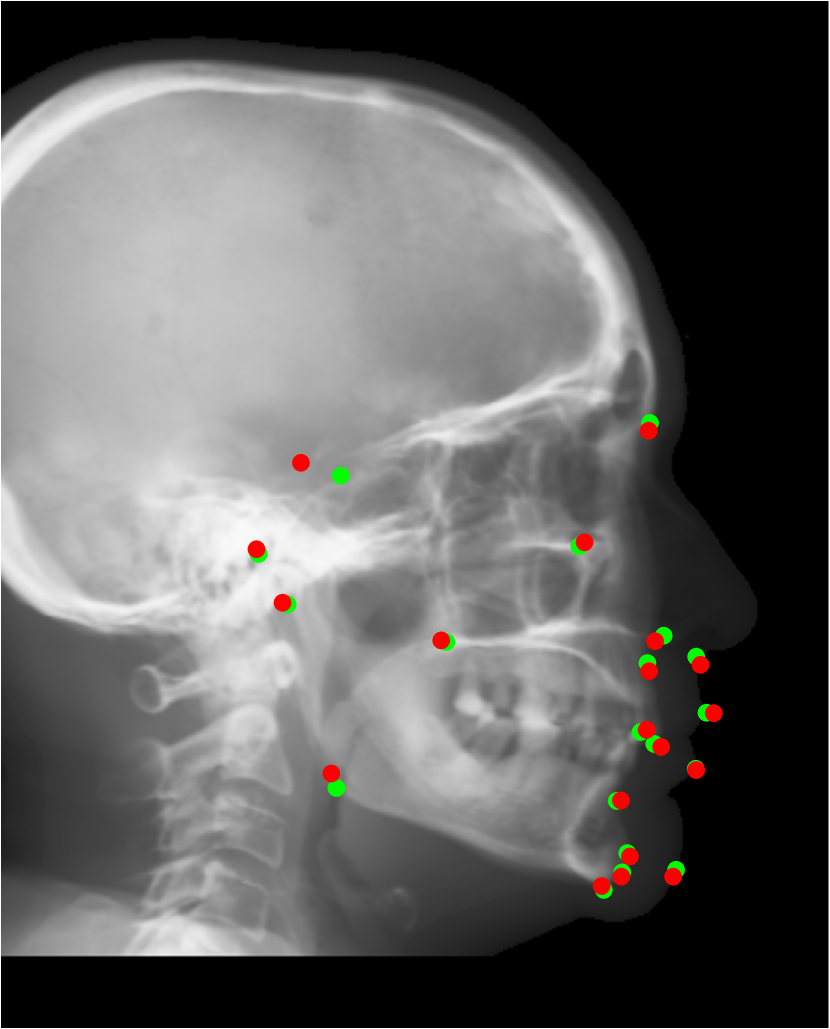

Refer to caption

Fig. 15: Accuracy comparison of different cephalometric landmark detection algorithms [16, 27, 1, 40, 7, 46] on ISBI Testset1 and Testset2.

To validate the efficacy of our proposed automatic landmark detection algorithm, it is compared with other state-of-the-art algorithms on the benchmark ISBI data (Testset1 and Testset2). The SDRs of different algorithms [16, 27, 1, 40, 7, 46] in different precision ranges for Testset1 and Testset2 are displayed in Fig. 15(a) and (b), respectively. Our proposed method achieves the 2 mm-SDRs of 86.7% and 73.7% on the ISBI Testset1 and Testset2, respectively, which is comparable to the best accuracy methods [7, 46]. However, our method is more efficient than [7] and has a simpler architecture than [46].

Fig. 16: Landmark detection on synthetic cephalograms. Cephalograms in the top row are obtained by different synthesis methods from 3D volumes for the first patient with pix2pixGAN for SR. The second row shows Type I synthetic cephalograms with different SR methods. The 3rd and bottom rows are Type I and Type II synthetic cephalograms respectively from three example patients with pix2pixGAN for SR. The green (reference) and blue labels are manual detection landmark positions in Type I and Type II synthetic cephalograms respectively, while the red labels are automated detection landmark positions in each cephalogram.

Our proposed landmark detection method is applied to detect landmarks in synthetic cephalograms. The results of three example patients are displayed in Fig. 16. Cephalograms in the top row are obtained by different synthesis methods from 3D volumes for the first patient with pix2pixGAN for SR. The second row shows Type I synthetic cephalograms with different SR methods. The 3rd and bottom rows are Type I and Type II synthetic cephalograms respectively from three example patients with pix2pixGAN for SR. The green and blue labels are manual detection landmark positions in Type I and Type II synthetic cephalograms respectively, while the red labels are automated detection landmark positions in each cephalogram. The green labels are used as the reference. The overall SDRs of the landmarks in different types of synthetic cephalograms on the test patients are displayed in Tab. 4. The last row SDRs are calculated from manual detection (blue) landmarks in Type II synthetic cephalograms w. r. t. reference landmarks, while others are from automatic detection (red) landmarks w. r. t. reference landmarks.

For RayCast in Fig. 16(a), many automatic detection landmarks exceed the 4 mm precision range such as the landmarks of anterior nasal spine, gonion, porion and articulare. According to Tab. 4, overall only 45.6% landmarks are detected within the 4 mm precision range by the automatic landmark detection algorithm. For MIP100 in Fig. 16(b), the landmarks of sella, porion, articulare have very large deviations from the reference landmarks. Overall, it achieves 47.4% 2 mm-SDR and 81.5% 4 mm-SDR. Figs. 16(c) and (g) are the cephalograms synthesized by our Type I synthesis with the original sigmoid transform and the modified sigmoid transform, respectively. These two synthetic cephalograms have subtle difference in the soft-tissue areas. As a result, the detected incision superius and lower lip positions exceed the 4 mm range in Fig. 16(c) while they are well detected within the 2 mm precision range in Fig. 16(g). This demonstrates the benefit of the modified sigmoid transform.

In Figs. 16(d)-(f), the landmark detection accuracies are very close to each other for the other 18 landmarks except for the sella landmark. The point-to-point errors are 9.77 mm, 4.57 mm, and 1.65 mm respectively in Figs. 16(d)-(f) for the sella. Tab. 4 indicates that overall 66.7% landmarks are detected within the 2 mm precision range for bicubic interpolation. For ESRGANRDB and ESRGANRRDB using ILR patches, the 2 mm-SDR rises to 70.2% and 71.9%, respectively. Nevertheless, pix2pixGAN achieves the best 2 mm-SDR 75.4% among different SR methods for Type I synthesis. Therefore, different SR methods have an influence on the landmark detection.

For Type I synthesis, two more cephalograms are displayed in Figs. 16(h) and (i). Overall, 93.0% automatic detection landmarks are overlapped with the reference landmarks within the precision range of 4 mm, with a few exceptions such as the sella landmark in (g), the porion in (h), and the incision inferius and subnasale landmarks in (i) beyond 4 mm. Particularly, 75.4% automatic detection landmarks are within the 2 mm clinical acceptable precision range. This indicates that the automatic landmark detection algorithms learned from real conventional cephalograms can be applied to our Type I synthetic cephalograms.

For Type II synthetic cephalograms in Figs. 16(j)-(l), all the manual detection (blue) landmarks are overlapped with the reference landmarks within the distance range of 4 mm, indicating that the landmark positions in the Type II synthetic cephalograms have no impactful position shift from those in Type I synthetic cephalograms. The majority (80.7%) of the automatic detection (red) landmarks are also overlapped with the reference landmarks within the 4 mm precision range. However, more automatic detection landmarks in Type II synthetic cephalograms are outside the 4 mm range than those in Type I synthetic cephalograms, for example, the anterior nasal spine landmark in (j), the orbitale landmark in (k), the incision inferius landmark in (l), the nasion landmarks in (k) and (l), and the gonion landmarks in (j)-(l). The 2 mm-SDR also decreases from 75.4% to 50.9%.